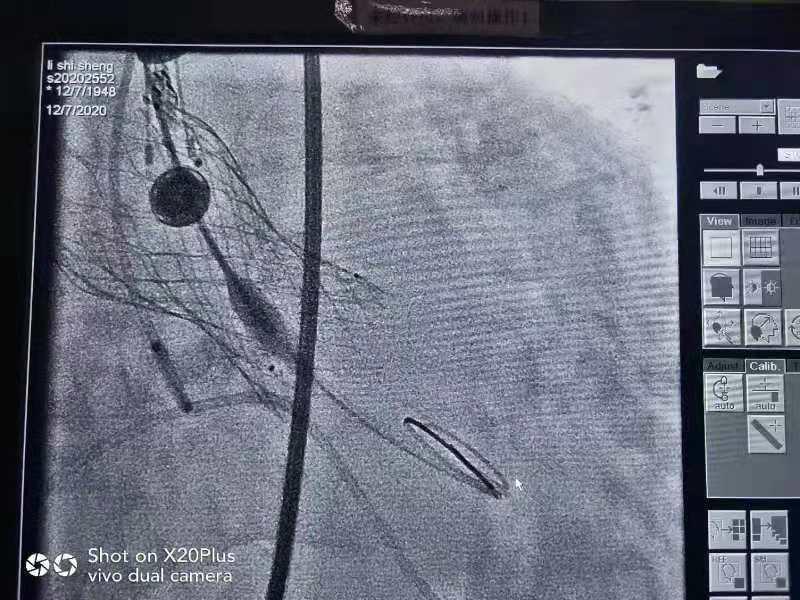

带支架的主动脉瓣

支架释放成功后

胸心血管外科团队经过药物控制肺部感染和手术前的精心准备和风险评估,12月7日上午,经过95分钟的奋战,经股动脉微创的方式扩张开狭窄的主动脉瓣,将一枚23号人工主动脉瓣膜植入、代替原病变的主动脉瓣开始正常工作。植入位置恰好、各项指标正常,将近70mmHg的跨主动脉瓣压差瞬间恢复至17mmHg,心脏功能恢复正常。